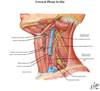

Cervical Plexus

- formed by branches of ventral rami C1-4

- Supplies:

Nuchal (neck) muscles

diaphragm muscle

infrahyoid (strap) musculature

skin of head/neck/chest

-superficial branches (sensory only):

lesser occipital n. - C2

great auricular n. - C2,3

transverse cervical n. - C2,3

supraclavicular n. - C3,4

-Deep branches include:

Motor to prevertebral ms. - ventral rami C1-4

Motor to levator scapula and ant, middle, post scaleni

Motor to infrahyoid muscles via ansa cervicalis – ventral rami C1-3

Motor & sensory to diaphragm via the phrenic n. - C3-5 ventral rami

Sensory to SCM & trapezius- ventral rami C2,3 (NOT MOTOR, ARE SENSORY) (pain & proprioception)